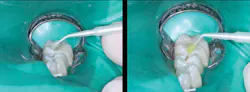

Figure 5: Glutaraldehyde placed for two one-minute applications and suctioned off (left) followed by your choice of bonding agent (right)

Figure 6: Finished restoration. Restorations accomplished in this manner will not have postoperative tooth sensitivity.